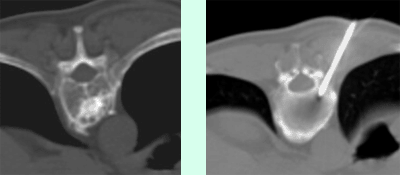

Abbildung (1a) CT eines kleinen HCC (Pfeil) bei einem Patienten mit Leberzirrhose (1b) In der Verlaufskontrolle 6 Monate nach Radiofrequenzablation zeigt sich ein nekrotisches Areal (Pfeil) ohne Hinweis auf Resttumor im Bereich des ehemaligen HCC. (1c) 4 Jahre später ist das Nekroseareal (Pfeil) deutlich kleiner. Ein Rezidiv-Tumor ist weiterhin nicht vorhanden.

Abbildung (2a) CT einer Patientin mit einer einzelnen kleinen kolorektalen Rezidiv-Lebermetastase im rechten Leberlappen (Pfeil). (2b) CT-gezielte Platzierung der Radiofrequenznadel mit der Spitze im Bereich der Metastase (2c) In der Verlaufskontrolle zeigt sich der Behandlungserfolg mit einem Nekroseareal (Pfeil) im Bereich der Metastase ohne Hinweis auf einen Resttumor.